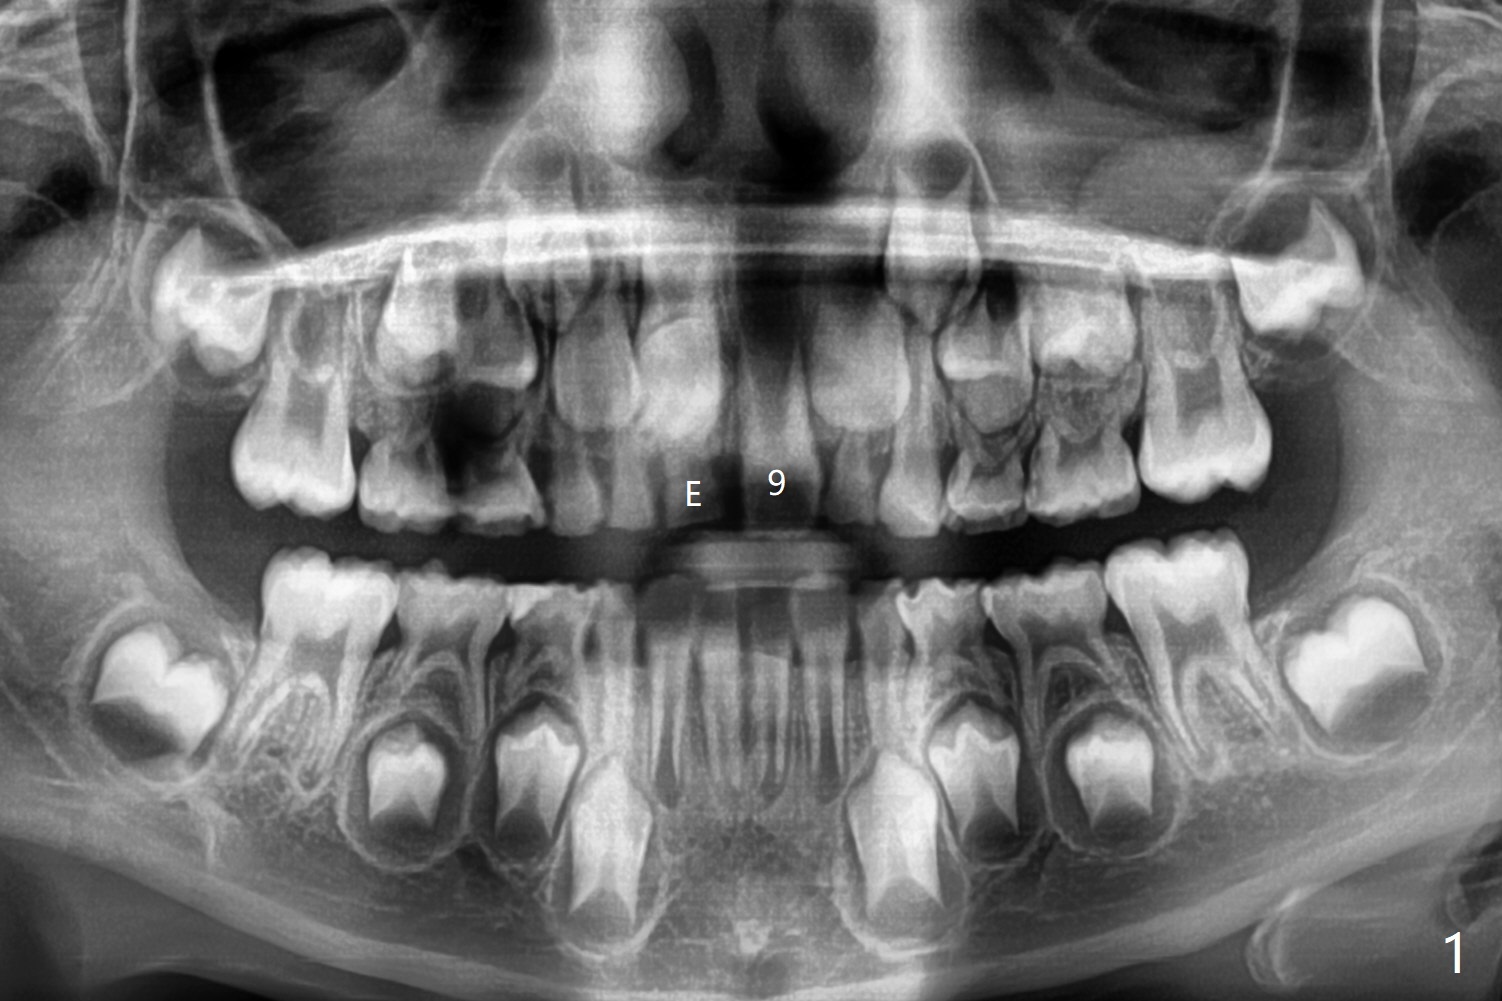

8岁男,右上乳中切牙滞留(图一,二:E),全景片,根尖片显示多生牙(图一,二:*),CT表明它位于腭侧(图三:P)。病人将今天(八岁八个月)回来拔除,腭侧牙龈缘切口应该容易暴露。